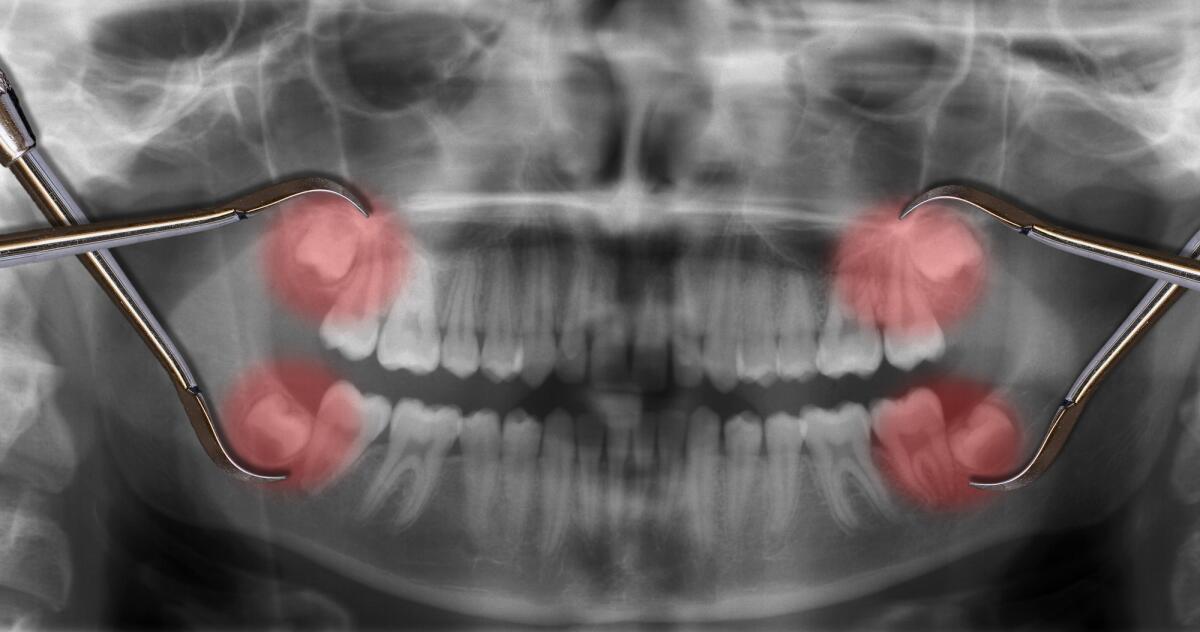

- По сравнению с другими зубами, зуб мудрости имеет большее количество корней — их количество может доходить до 5. Эта особенность нередко становится причиной проблем при его удалении.

- Значительная изогнутость корней, затрудняющая прочистку и пломбирование каналов.

- Позднее прорезывание — чаще после 17−18 лет.